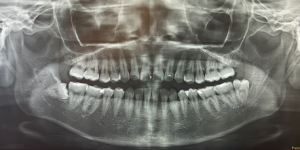

エックス線での撮影後、歯周病の検査を行い、以下の項目をチェックしました。

その後エックス線をよく確認したところ、歯と歯の間の複数箇所に虫歯があり、プラスチックで治療した痕(白い部位)がありました。

プラスチックは茶色く変色し、縁は黒ずんでいます。歯と歯の間は、凹んでいるためフロスも通しづらい状態でした。さらに詳しく調べるために口腔内エックス線も撮影し、詰め物の大きさを確認することにしました。